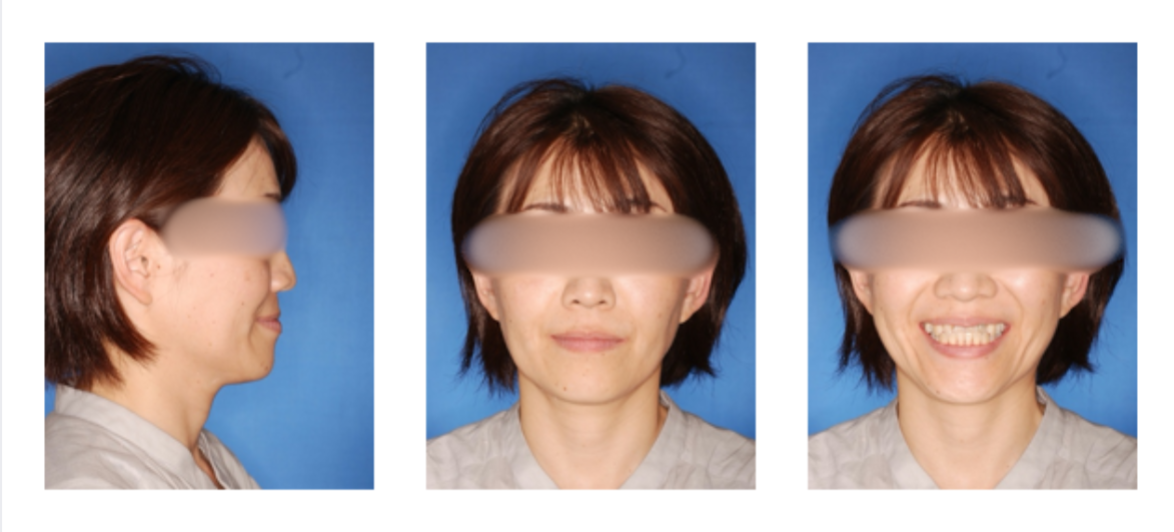

上顎前突の症例

初診時

治療終了時

治療終了時から2年経過時(保定開始時から2年経過時)

初診

治療終了時

治療終了後から2年経過時

(保定開始時から2年経過時)

| 年齢・性別 |

20代 女性 |

| 主訴 |

前歯が出ているのを治したい。 |

| 治療について |

上は前歯をかなり下げるために小臼歯、更に大臼歯を抜歯、下はガタガタを治すため、小臼歯の抜歯を行いました。 |

| 治療期間 |

2年 |

| 治療費用 |

1,310,100(検査料と診断料、全ての調整料を含みます) |

| 治療に用いた主な装置 |

マルチブラケット装置(上顎舌側、下顎唇側の装置)、歯科矯正用アンカースクリュー |

| 抜歯部位 |

上顎両側第一小臼歯、第二大臼歯、下顎両側第二小臼歯、第三大臼歯 |

| 通院回数 |

21回 |